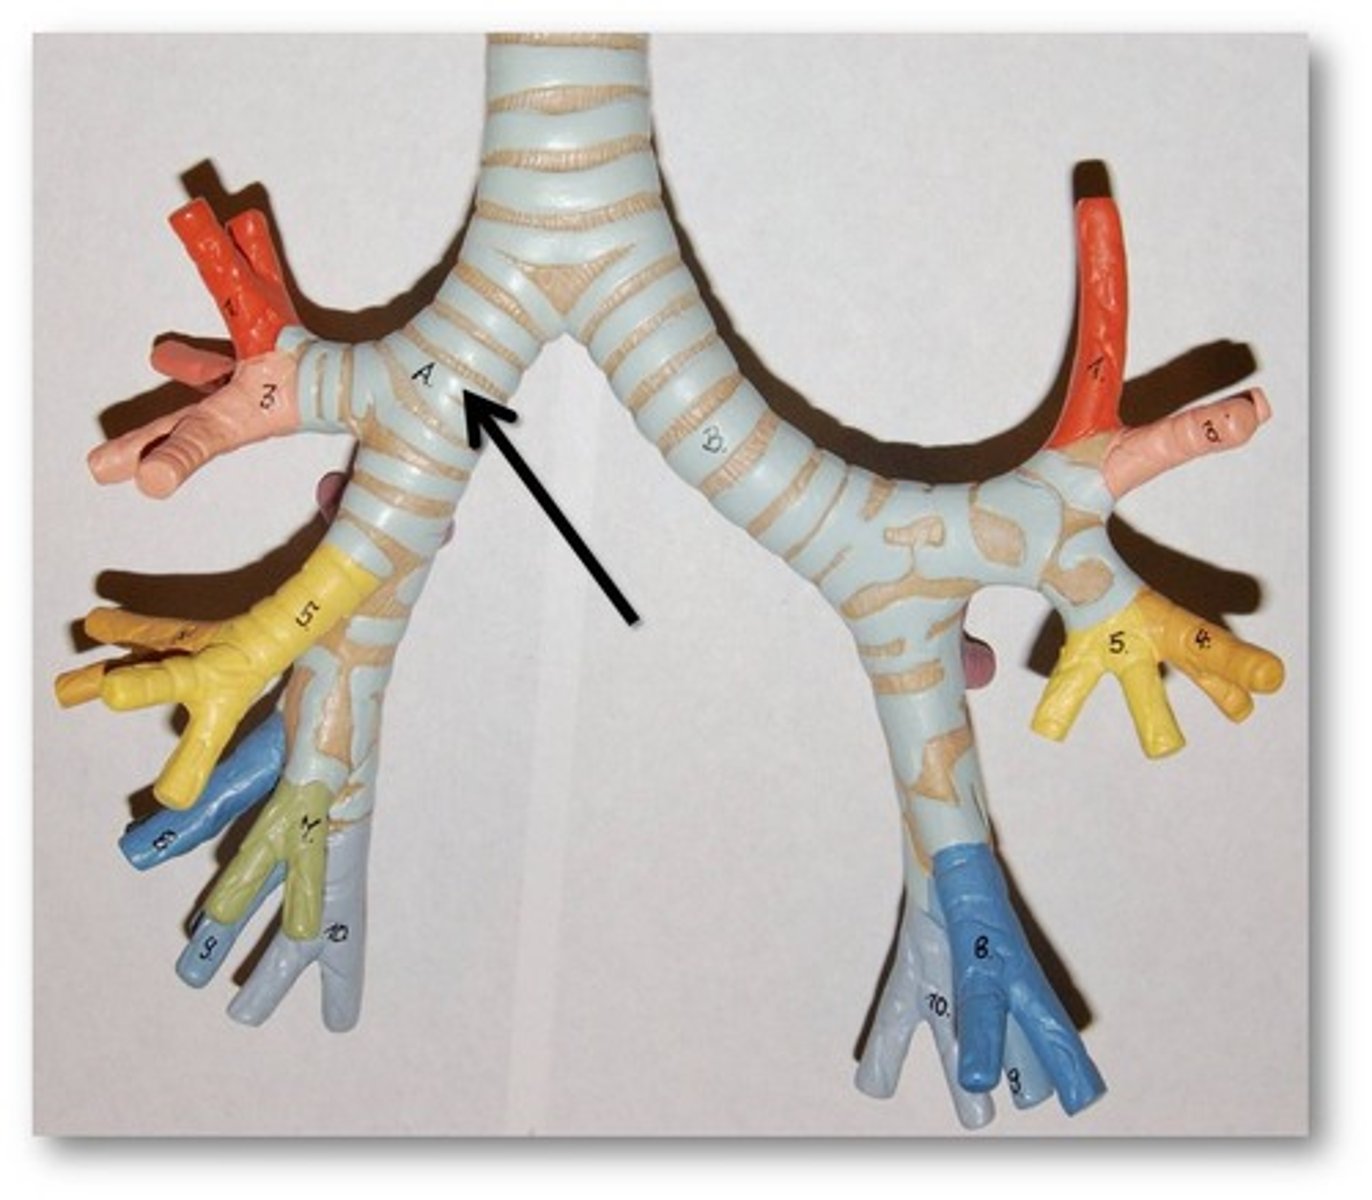

Primary bronchus

Secondary bronchi

Any of the tertiary bronchi

Hilum